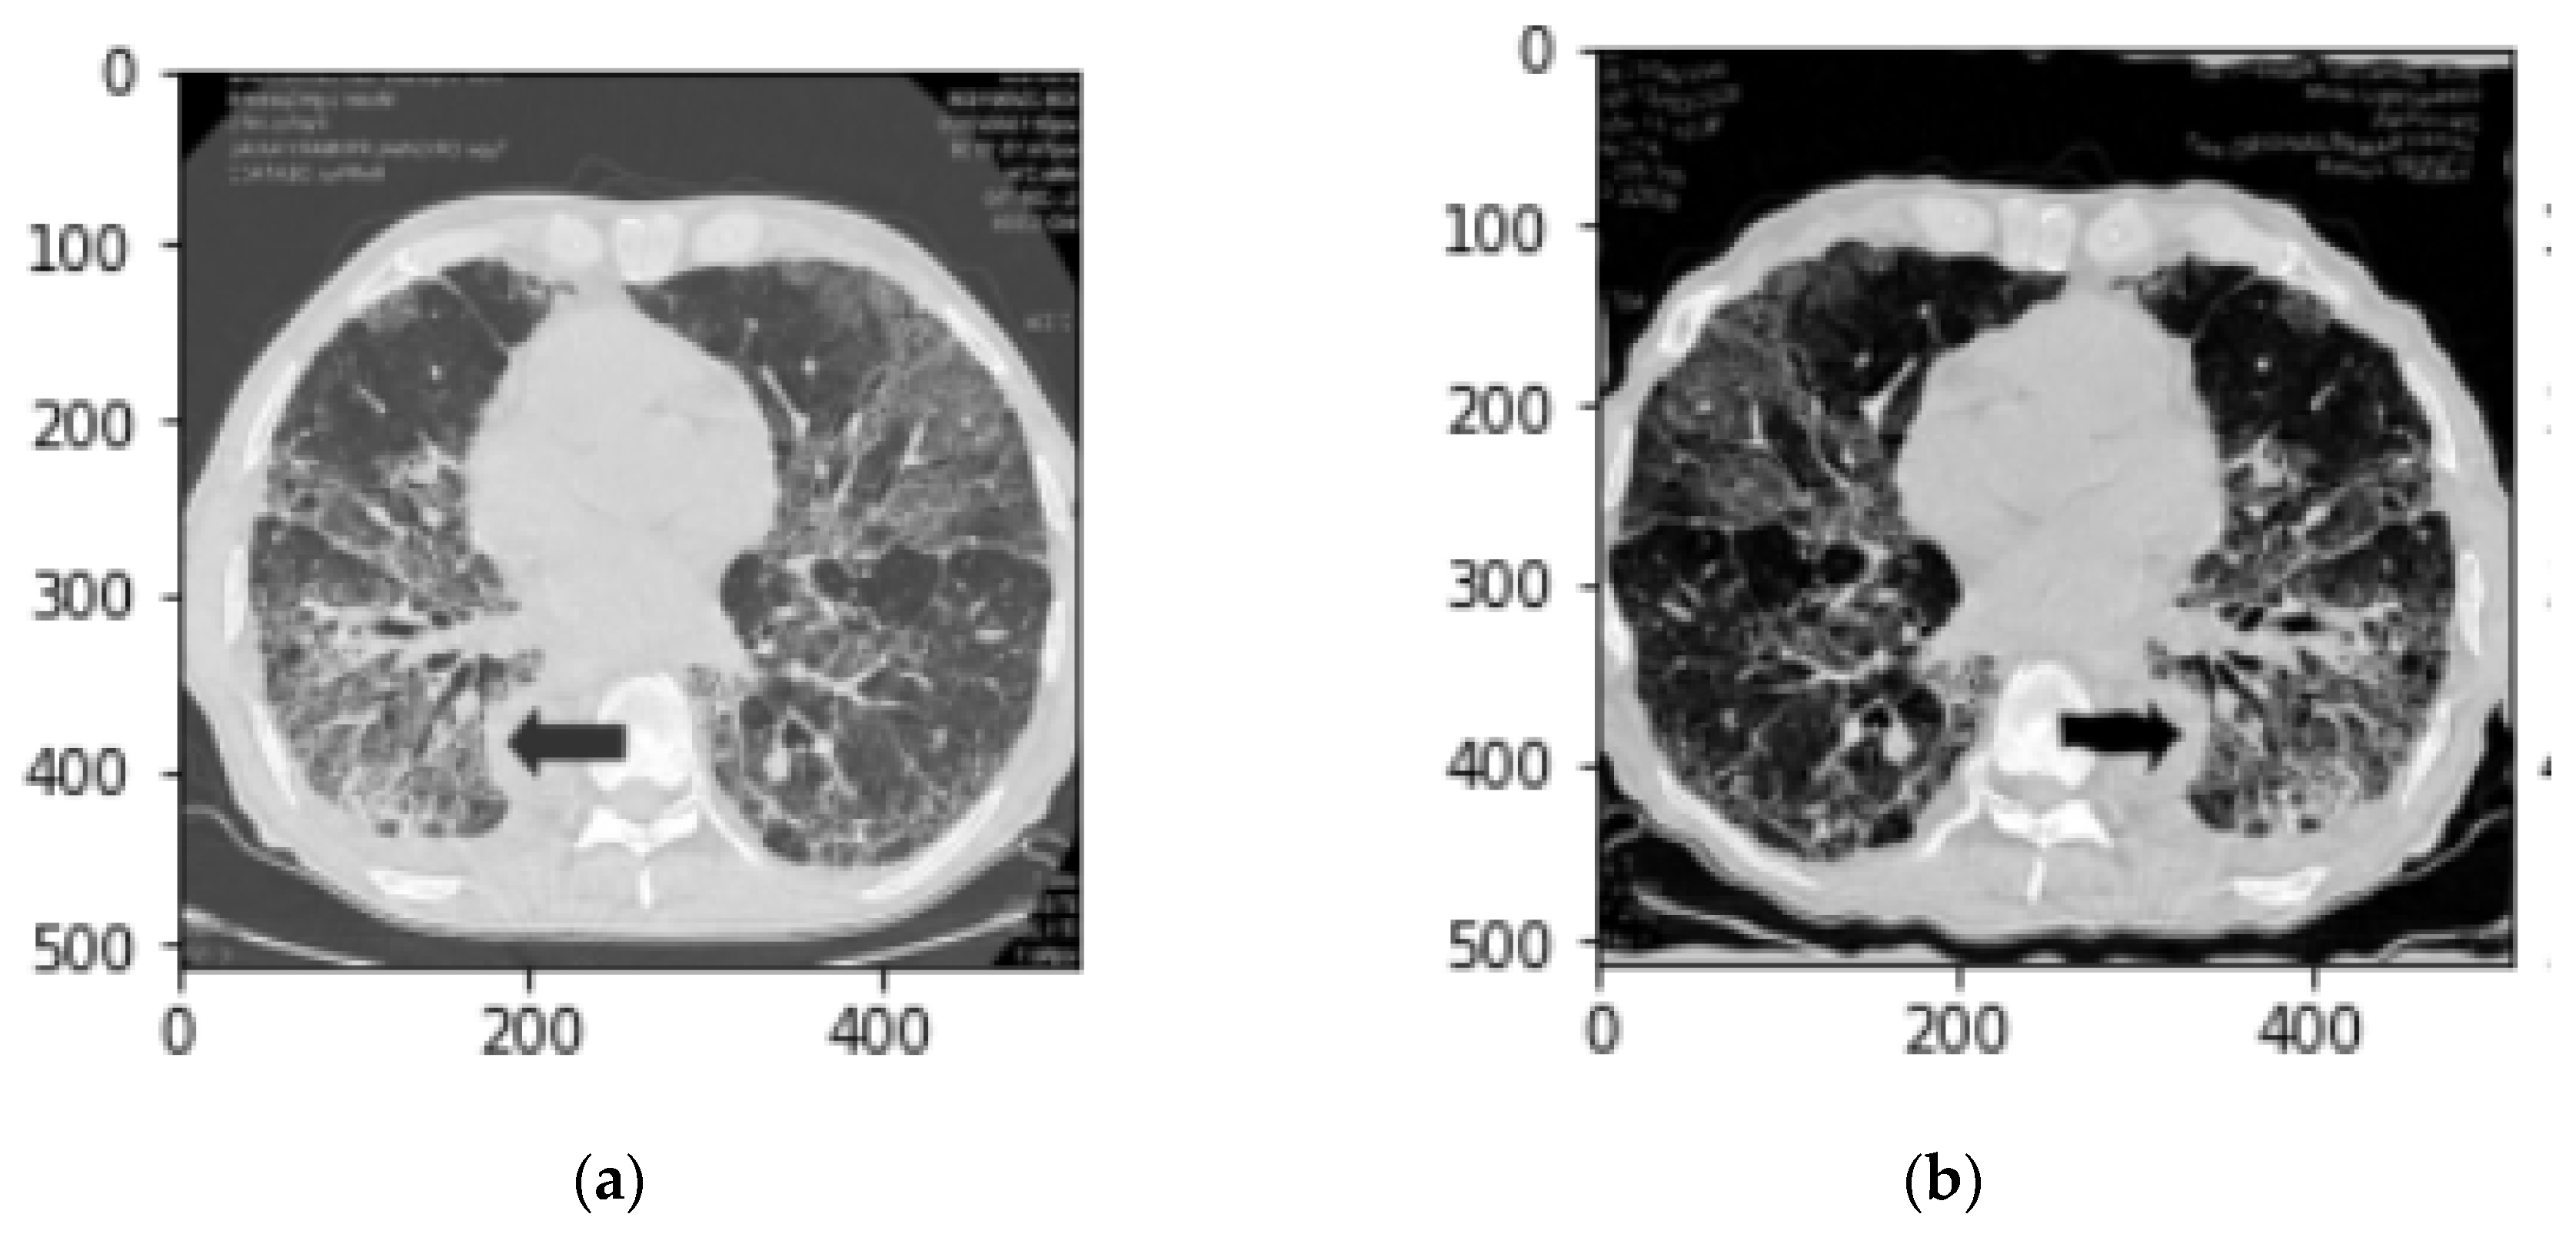

2.4. Image preprocessing

After observing the output of the lung segmentation model, it was noted that in several cases with sever disease infection, small percentage of the lung may be missing from the segmentation as shown in Figure 5-a, which are typically represent disease infection area. In order to include or recover the missed lung area if the lung segmentation error is visually observed from our GUI, the user (i.e., radiologist) can call an image a specially-designed post-processing function that applies a unique conventional image processing algorithm inspired by the rolling ball algorithm [24] to automatically correct segmentation error. This algorithm starts with extracting the lung contours followed by several steps and morphological filters such as disk drawing, filling holes, median, and erosion operations. As shown in Figure 6, it can convert a jagged and rough lung boundary as shown in Figure 6-a to a smooth one which covers the previously missed lung area as shown in Figure 6-b. While it might lead to a small over-segmentation in some cases, the previously missed area contains very important infected lesions that can significantly affect the assessment of sever cases.

Figure 6. (a) lung segmentation mask (b) post-processing lung segmentation.